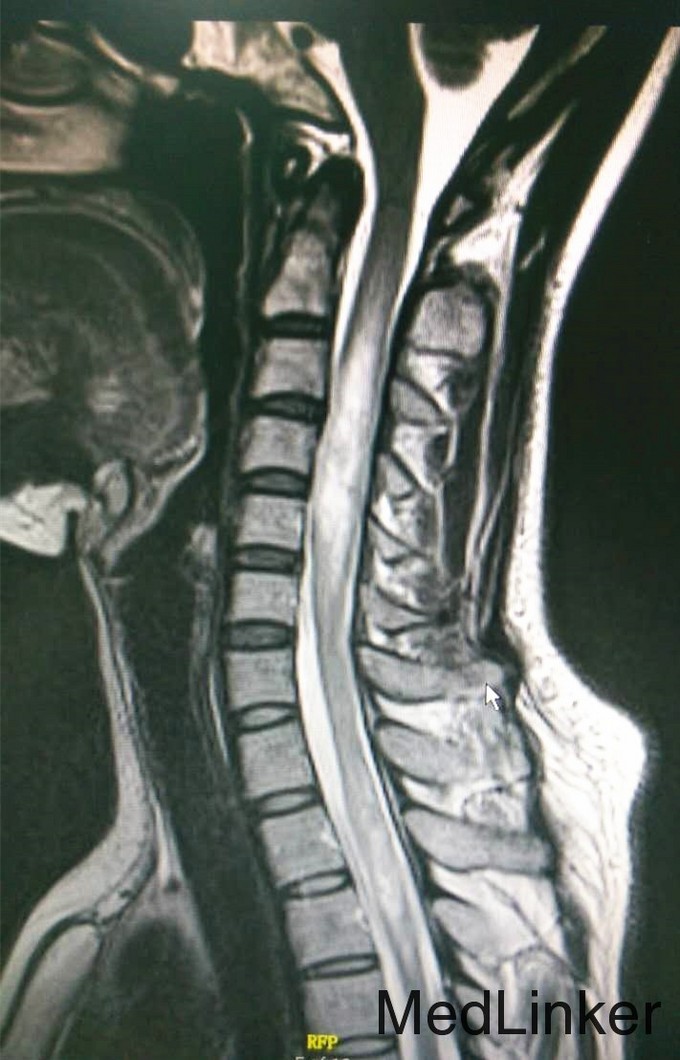

初步诊断:脱髓鞘病 诊断依据:1.患者反复肢体麻木,疼痛,无力,曾有截瘫、窜电感,本次以右上肢瘫痪、麻木为主要症状。2.查体:左上肢肌力IV级,右上肢肌力II级,右上肢肌张力减弱,右侧C3以下肢体痛觉减退,左侧病理征阳性。3.症状反复发作,既往诊断脊髓炎,脱髓鞘病,激素治疗后症状缓解。 诊疗计划: 1、完善入院常规检查如血常规、颈段脊髓MR平扫+增强等。 2、给予患者营养脑神经,激素等对症支持治疗。